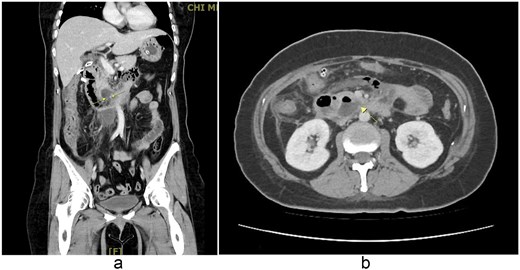

Laparoscopic lavage and abscess drainage yielded about 150 mL of turbid ascites in the subhepatic retroperitoneum without definite perforation, suggesting a sealed micro-perforation. The Estimated blood loss was 100 mL. Postoperatively, she received PCA, nasogastric drainage, parenteral nutrition, and antibiotics (cefazolin plus metronidazole, later flomoxef, then piperacillin–tazobactam). Persistent bilious drainage was noted. On postoperative day 2, she developed fever (38.4°C), leukocytosis (9790/μL), hypokalemia (2.7 mmol/L), and elevated CRP (154 mg/L). Despite therapy, bile leakage and right upper quadrant pain persisted. Follow-up CT on 2 September 2025 revealed probable perforation at the third portion of the duodenum with retroperitoneal abscess (Fig. 2). At her request, she was transferred to our hospital for further surgical management.

(a, b) Contrast-enhanced abdominal CT scan (coronal and axial views, 2 September 2025). Imaging demonstrates extraluminal air bubbles and a retroperitoneal abscess (arrow) adjacent to the third portion of the duodenum, consistent with duodenal perforation.